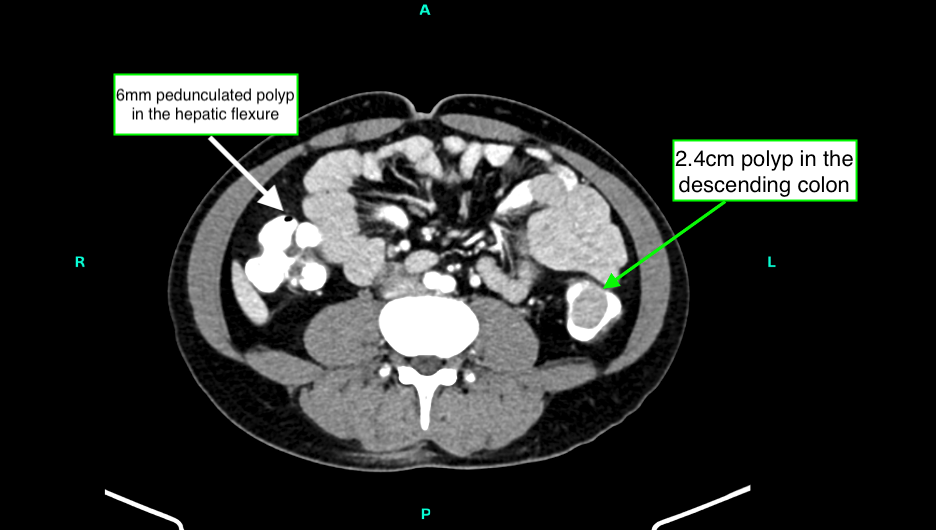

A contrast-enhanced CT scan of the abdomen and pelvis (portal venous phase) revealed highly suggestive findings of innumerable intraluminal polypoidal lesions carpeting the entire colon, with specific larger polyps noted in the descending colon (2.4 cm) and hepatic flexure (6 mm), respectively (Figure 1). No metastatic lesions or desmoid tumors were identified.

Figure 1. Contrast-enhanced axial CT abdomen demonstrating a large 2.4cm polyp in the descending colon (green arrow) and a 6mm pedunculated polyp in the hepatic flexure (white arrow).